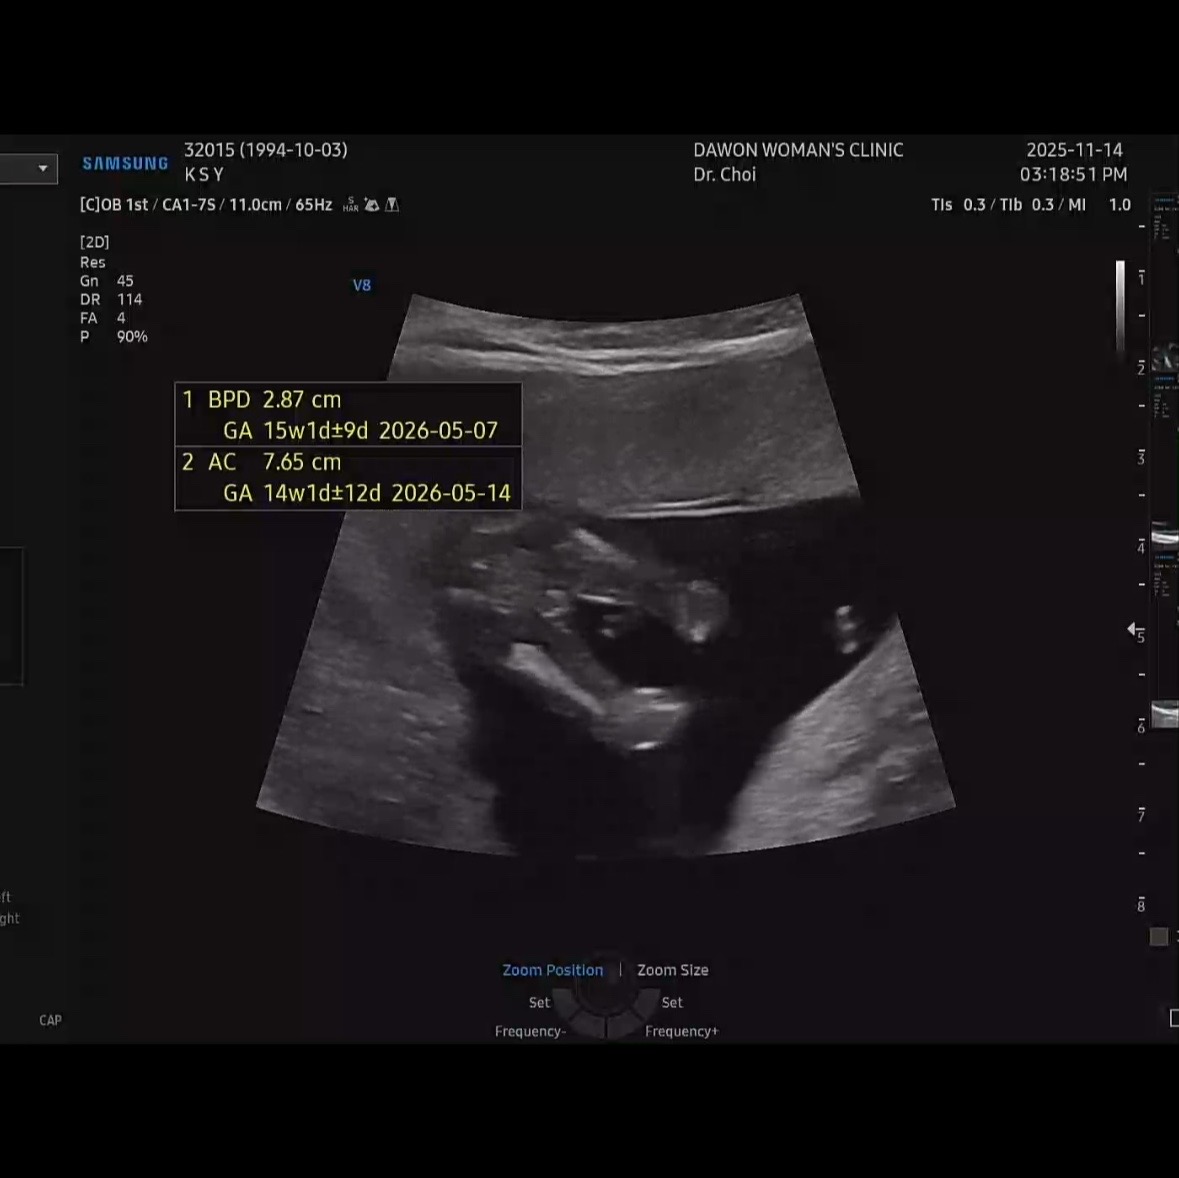

다리 사이에 있는게 제가 생각하는게 맞을까요? 친구의 경험으로는 딸은 저런것도 아예없었다하는데.. ㅜㅜ 저런 모양도 보신 분 계실까요? 14주 2일차에 찍은 초음파 사진입니다.